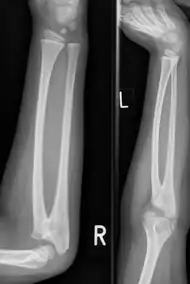

![]() | |

| Congenital radioulnar synostosis in a 7 year old boy | |